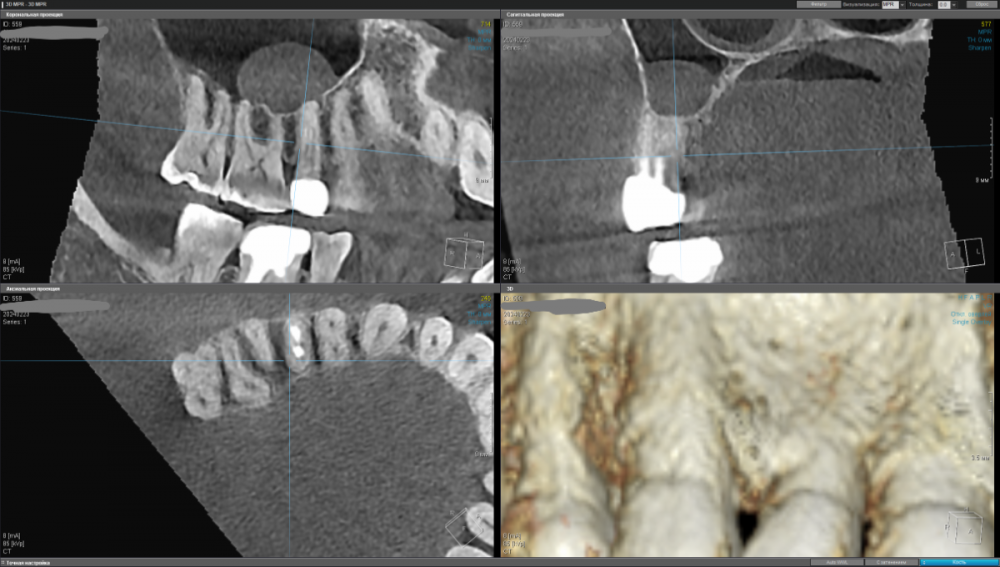

kamacho Опубликовано 24 февраля, 2024 Автор Поделиться Опубликовано 24 февраля, 2024 Попробую привлечь ваше внимание дополнительными снимками. Вопросы которые я себе задаю когда смотрю на КТ: 1) Между 14 и 15 зубом, это убыль фуркации или артефакт при съемке кт ? 2) В районе 37 ого зуба это артефакт или кариес ? Я пытаюсь санировать ротовую полость уже наверное лет пять, и никогда не удается решить проблему. Прошел множество клинник (наверное штук 5-6, включая 1 зарубежную). Но после попыток лечения, возникает одна и таже проблема, как только начинаю добавлять углеводы(не сладости) в рацион, какой-то очаг инфекции дает о себе знать. Буду очень признателен если поможете советом или догадкой. Ссылка на комментарий

Carioznik Опубликовано 25 февраля, 2024 Поделиться Опубликовано 25 февраля, 2024 15.02.2024 в 18:43, kamacho сказал: есть ли показания для лечения этого зубика? По идее есть, но нужно разбираться 15.02.2024 в 18:43, kamacho сказал: Могут ли не до конца пролеченные корни вызывать такую симптоматику ? Нет 17 часов назад, kamacho сказал: Между 14 и 15 зубом, это убыль фуркации Нет. Похоже, что на 14 есть кариес. Возможно это и причина кровоточивости и запаха. Но нужно смотреть настоящую КТ , а не скрины. 18 часов назад, kamacho сказал: районе 37 ого зуба это артефакт или кариес ? Больше на артефакт похоже, но это не точно: нужно смотреть настоящую КТ , а не скрины 1 Ссылка на комментарий